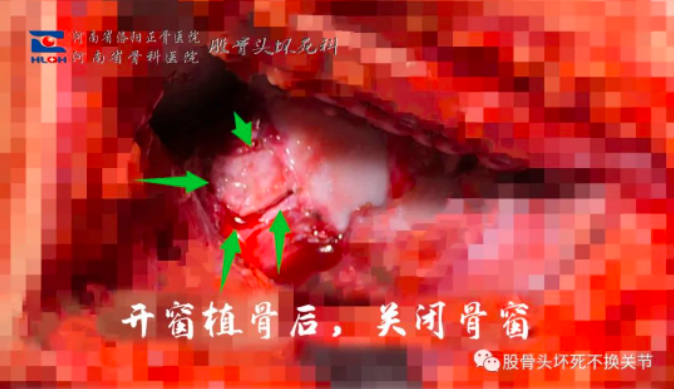

左侧股骨头:有症状、空洞、大范围骨髓水肿、滑膜增生,予以滑膜切除、减压、植骨治疗。